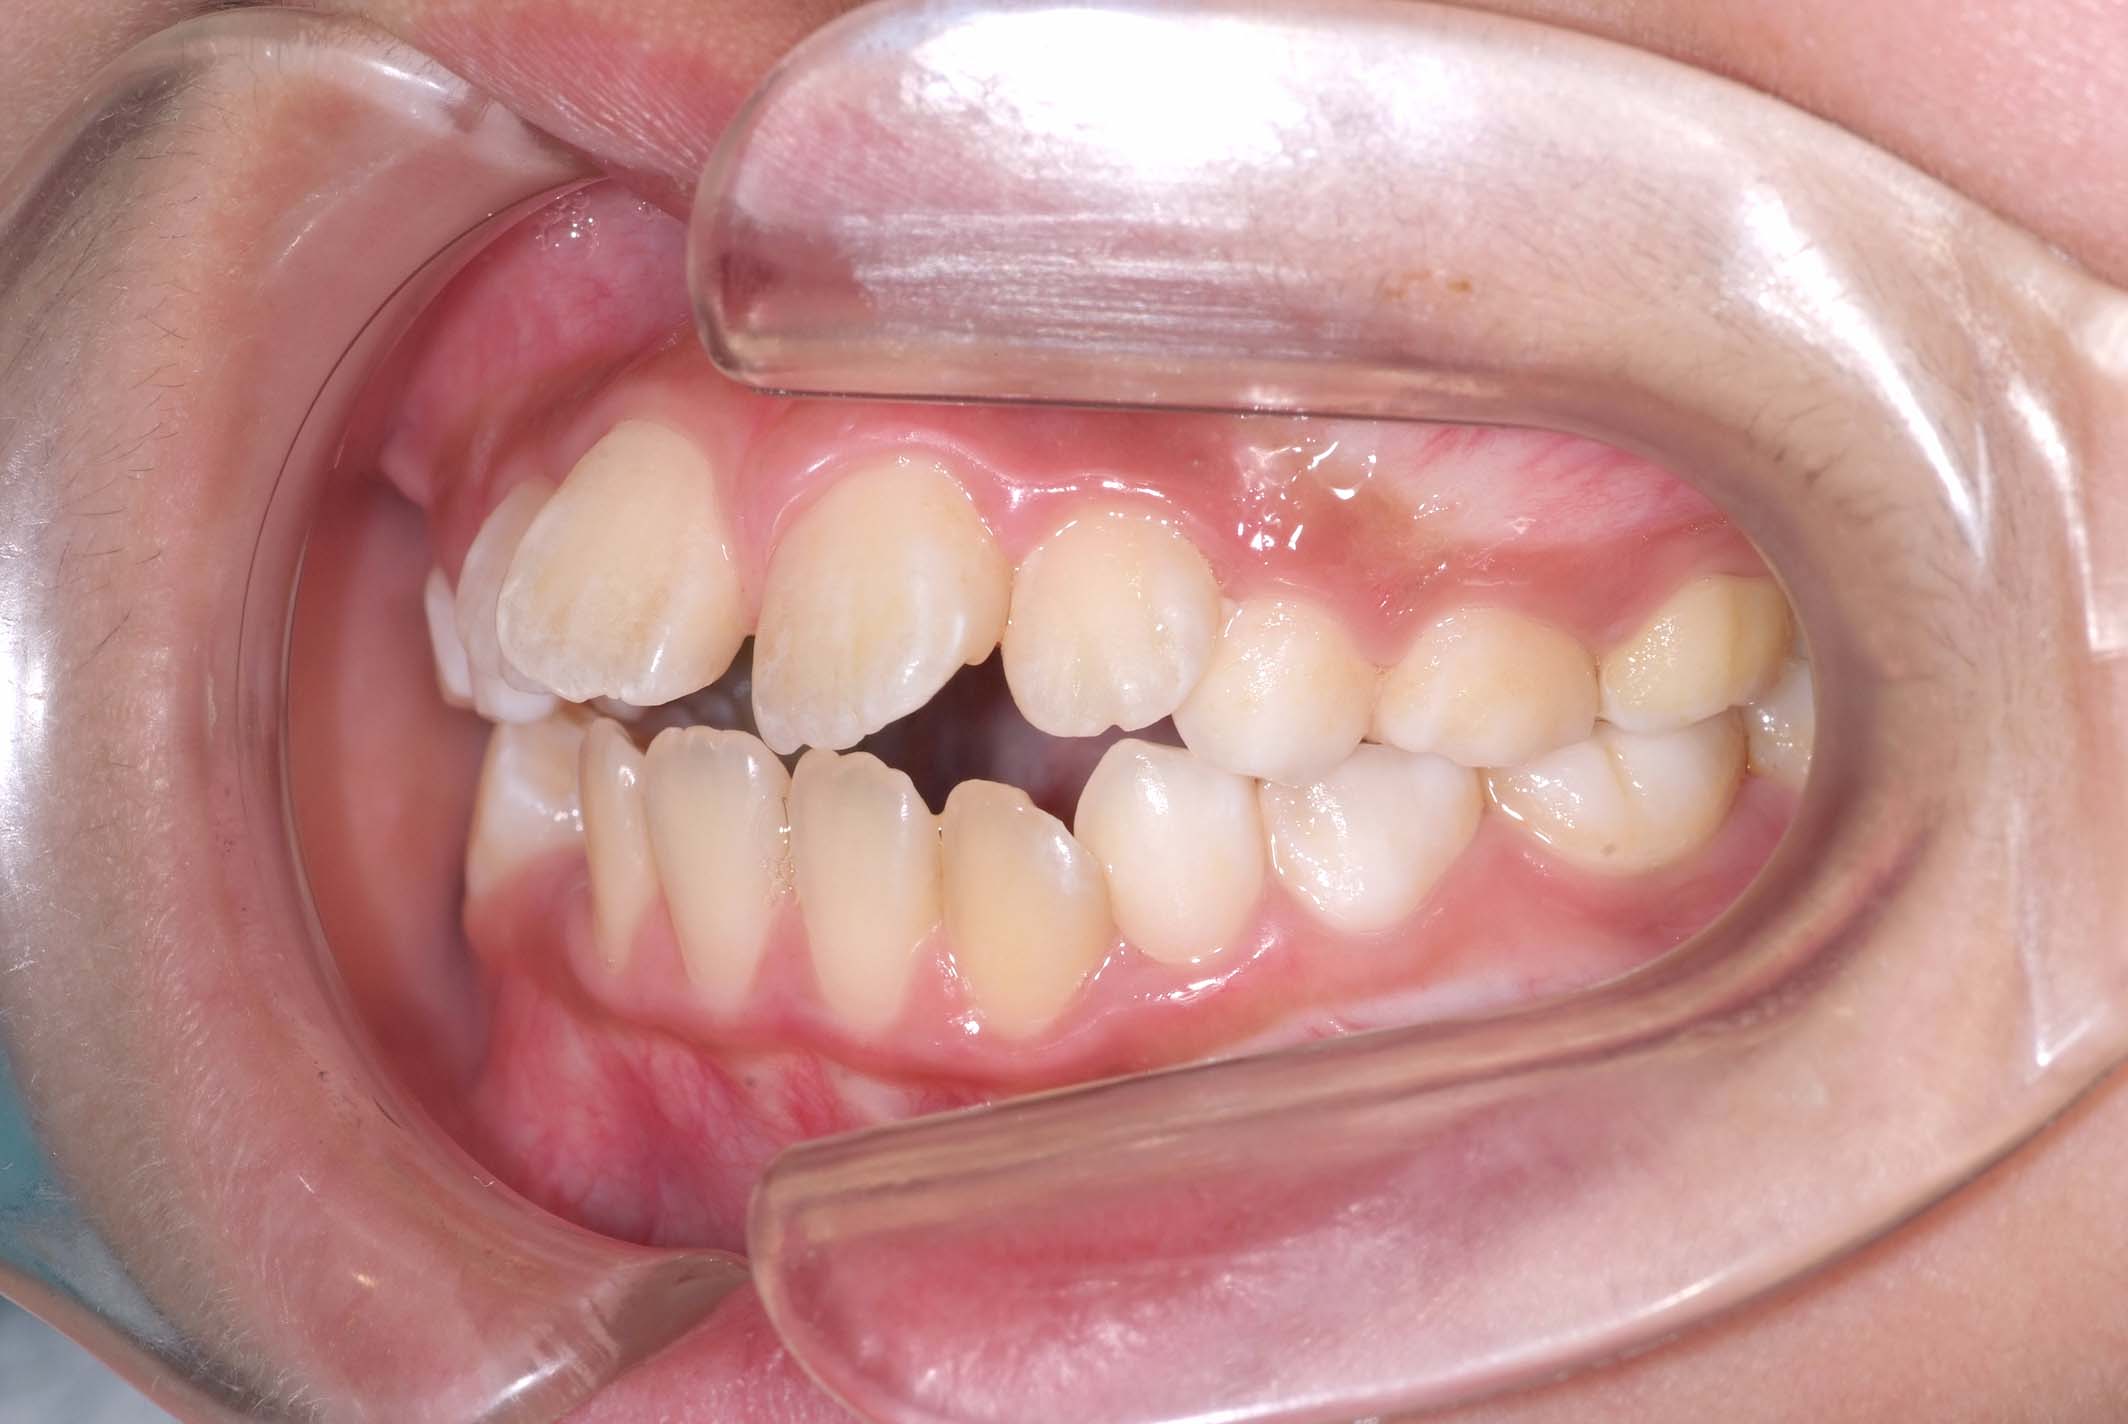

初診時年齢8才の女子で、前歯部開咬を気にして来院されました。

検査の結果、前歯部開咬と正中離開と上下顎前歯唇側傾斜を伴うアングルⅡ級1類不正咬合と診断しました。

前期治療は、リンガルアーチで正中離開を改善し、その後は歯列矯正用咬合誘導装置(マイオブレース)を使用して舌のトレーニングを行いました。後期治療は、上下左右4番を抜歯の上、セルフライゲーションブラケット装置(クリアティ・ウルトラ)で行いました。治療期間は前後期合わせて6年6ヶ月でした。通院回数:60回。